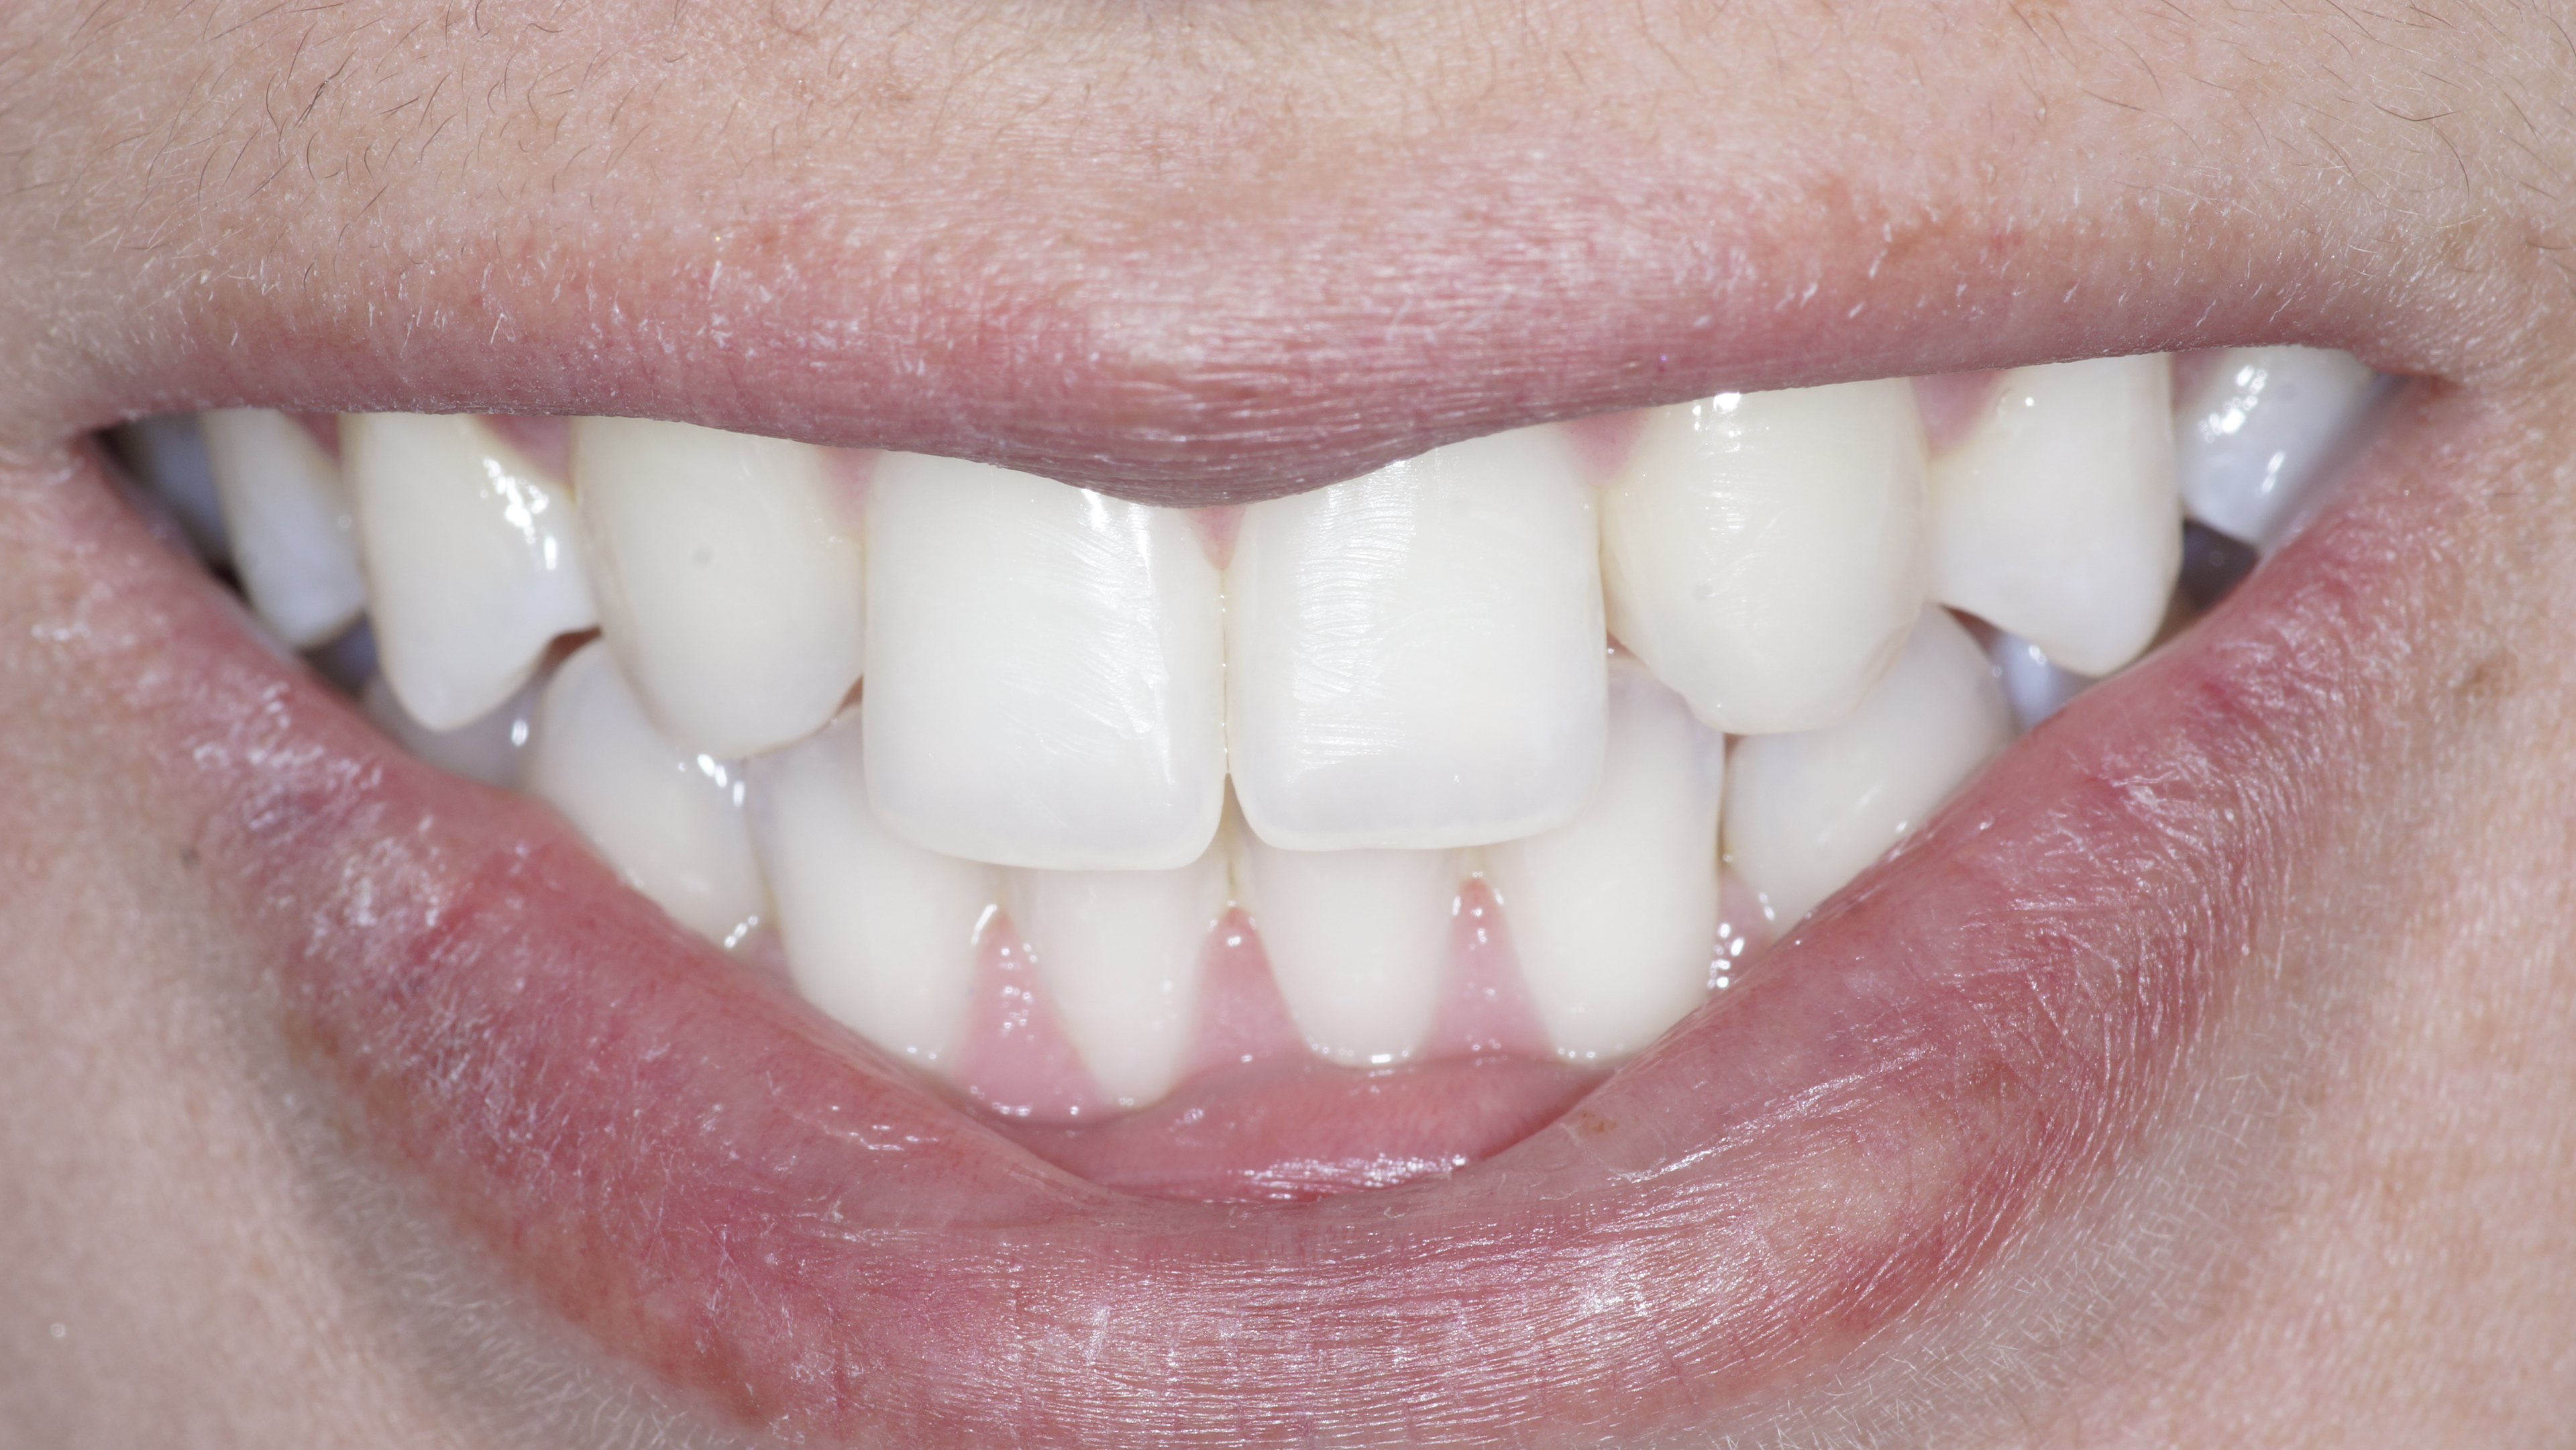

E-max Final post-op

Immediate port-op - Nice shade